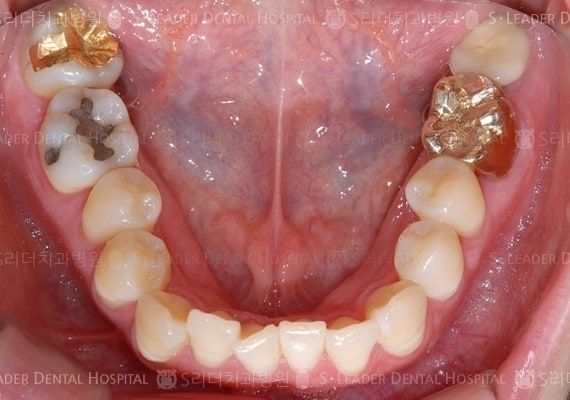

20140425050415_1_923152.JPG 20140425050415_2_522570.JPG

틀니임플란트,부분틀니,15년 10개월 경과